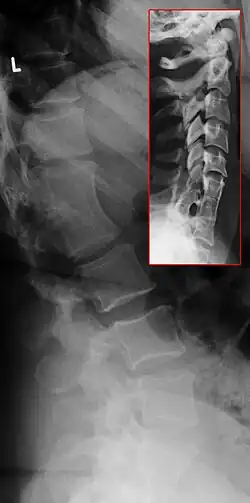

Röntgenaufnahmen Klippel-Feil-Syndrom L1/2 (großes Bild) und C6-Th1 (im roten Kasten). Die Bilder stammen vom selben Patienten.

In der Diagnostik des Klippel-Feil-Syndroms sind standardisierte Röntgenaufnahmen der Halswirbelsäule oft nicht möglich, weil die vorgesehene Standardposition vom Patienten aufgrund der Fehlbildung nicht eingenommen werden kann. Unterkiefer, Hinterhauptsbein und Foramen magnum können sich auf die Halswirbel projizieren. Seitliche Schichtaufnahmen in Beugung (Flexion) und Streckung (Extension) können – insbesondere bei Kindern, bei denen die Epiphysenfugen noch nicht geschlossen sind – hilfreich sein. Schnittbildgebungen wie Kernspintomographie (sollte aufgrund fehlender Strahlenbelastung besonders im Kindesalter vorgezogen werden) und Computertomografie sind besonders geeignet zur Beurteilung, ob eine Kompression von Nervenwurzel oder Rückenmark vorliegt.

In etwa 60 Prozent der Fälle liegen weitere Fehlbildungen der Wirbelsäule vor, meist Skoliose und Kyphose. Das Syndrom kann auch an mehreren Abschnitten der Wirbelsäule gleichzeitig auftreten (vgl. Röntgenbild). Ein Drittel der Patienten hat Fehlbildungen des Harntrakts. In 20 bis 30 Prozent der Fälle findet man einen ein- oder beidseitigen Hochstand des Schulterblattes (Sprengel-Deformität). Etwa 14 Prozent der Patienten haben angeborene Herzfehler.[2]